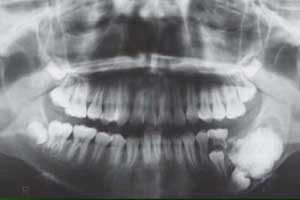

- визуализационные исследования – рентгенография, КТ, МРТ, ПЭТ-КТ — выполняются для того, чтобы выявить опухоль и точно определить размер, структуру, локализацию, оценить возможность озлокачествления;